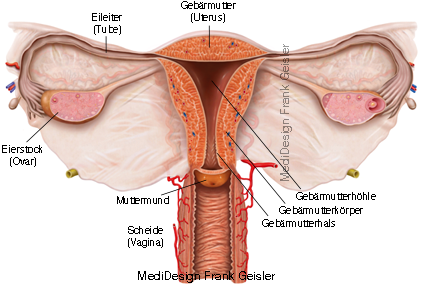

Geschlechtsorgane der Frau

Die inneren weiblichen Geschlechtsorgane sind Eierstock (Ovarium), Eileiter (Tuba uterina), Gebärmutter (Uterus) und Scheide (Vagina), die sich alle im Beckenbereich befinden. Die äußeren weiblichen Genitalorgane bestehen aus den großen Schamlippen (Labia majora), dem Kitzler (Clitoris), den kleinen Schamlippen (Labia minora), dem von ihnen eingeschlossenen Scheidenvorhof (Vestibulum vaginae) mit den hier mündenden Drüsen und der äußeren Öffnung der weiblichen Harnröhre (Urethra). Vulva (Pudendum femininum) bezeichnet die Gesamtheit der äußeren Geschlechtsorgane einer Frau.

Die Gebärmutter ist das weibliche Geschlechtsorgan, in welchem die befruchteten Eizellen vor der Geburt zu einem Embryo bzw. Fetus heranreifen.

Die Scheide ist ein etwa 10 cm langer Schlauch welcher den Penis beim Geschlechtsverkehr aufnimmt, durch den das Kindbei der Entbindung nach außen gelangt.

Längsschnitt durch die Beckenorgane und Geschlechtsorgane der Frau; Gräfenberg-Zone, G-Punkt, eine erogene Zone der Vagina

Das mandelförmige Ovar liegt intraperitoneal, ist allgemein 3 bis 5 cm lang und hat eine Dicke von 0,5 bis 1 cm. Es wird durch mehrere Haltebänder schräg am Beckeneingang fixiert. In diesem Organ erfolgt die Reifung und Bereitstellung der Eizellen, die in der Zeit zwischen dem Eintritt der Geschlechtsreife (Menarche) und dem Klimakterium durch den monatlichen Eisprung (Ovulation) ausgestoßen werden. Dabei erreicht ein Tertiärfollikel oder Bläschenfollikel (Graaf-Follikel) die Oberfläche des Ovars und platzt (Eisprung). Die Fransen (Fimbriae) des Eileiters umgreifen den Eierstock an der Stelle, wo wo der Eisprung stattfindet, um das ausgestoßene Ei aufzunehmen. Der Flimmerstrom und der Sog im Eileiter bewirken die Weiterleitung in Richtung Uterus.

Der Eisprung selbst dauert 3 bis 5 Minuten. Normalerweise erreicht die Eizelle zunächst die Ampulle des Eileiters, wo die mögliche Befruchtung stattfindet. Eine Eizelle soll nur 6 bis 24 Stunden befruchtungsfähig sein, während für Spermien im Eileiter 2 bis 4 Tage angegeben werden. In Ausnahmefällen kann der Aufnahmemechanismus in den Eileiter unterbleiben, so dass es bei einer Befruchtung zur Bauchhöhlenschwangerschaft (Extrauteringravidität) kommt. Die meisten Bauchhöhlenschwangerschaften entwickeln keinen Fötus. Die häufigste Extrauterinschwangerschaft ist die Eileiterschwangerschaft.

Der Restteil des geplatzten Follikels wird im Eierstock zum Gelbkörper (Corpus luteum) und gibt die Gelbkörperhormone (Progesteron) ab, während vor der Ovulation im Ovar die Bildung von Follikelhormonen (Estrogene) erfolgt. Diesen zweiphasigen ovariellen Zyklus von etwa 28 Tagen reguliert der Hypothalamus mit Steuerhormonen, die auf die Hypophyse wirken. Diese regt in der ersten Zyklushälfte mit ihrem follikelstimulierenden Hormon (FSH) das Ovar zur Produktion der der Follikelhormone an.

Die Gebärmutter bereitet mit ihrer Schleimhautveränderung während des Zyklus die Einnistung des Keimes vor und dient als Fruchthalter in der Schwangerschaft. Die Schwangerschaft nennt man Endometrium, die Muskulatur Myometrium und den Peritonealüberzug Perimetrium.

Schnittdarstellung Scheide und Gebärmutter mit Eileiter und Eierstöcke, Eireifung und Follikelsprung; Vulva erregt mit Kitzler und Uterus; Klitoris, ein aus Schwellkörpergewebe bestehendes Lustorgan der Frau

Die Vagina besteht aus einer häutig-muskulösen Wand, sie wird bei sexueller Erregung durch wässrige Transsudation aus dem Epithel befeuchtet, was man Lubrikation nennt. Die Bartholinschen Drüsen, welche bei Erregung ein schleimhaltiges Sekret absondern, münden in den Scheidenvorhof und befeuchten ihn. Das Vaginalsekret ist unter Einfluss des Sexualhormons Östrogen und einer speziellen Keimflora (Döderlein-Bakterien) sauer (pH-Wert 4 bis 4,5) und dient dem Schutz gegen aufsteigende Infektionen des weiblichen Genitaltraktes. Jede Störung dieses Vaginalmilieus steigert die Anfälligkeit gegen Infektionen und mechanische Reize. Es kann zu einer Scheidenentzündung (Kolpitis) mit Ausfluss (Fluor vaginalis) kommen. Bei der Geburt wird die Vagina zum Geburtskanal für das Neugeborene.

Bei der Gräfenberg-Zone, auch G-Zone sowie G-Punkt oder G-Spot, handelt es sich um eine erogene Zone in der Vagina. Bei manchen Frauen soll ihre Stimulation sehr schnell zu einem Orgasmus führen, andere empfinden diese jedoch als wenig oder nicht erregend. Die Zone liegt etwa 3 bis 5 cm vom Scheideneingang entfernt an der Vorderwand der Scheide, zur Bauchdecke hin, unmittelbar hinter dem Schambein. Sie ist etwa 2 cm im Durchmesser. Ein Merkmal des G-Punktes ist, dass sich das Gewebe an dieser Stelle rauh, gerippt oder fester anfühlt, während die übrige Scheidenwand glatt ist.